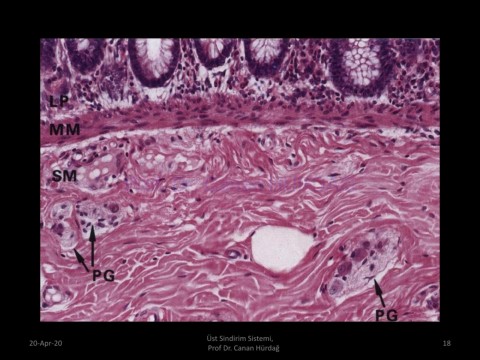

Page 18 - Sindirim Kanalı ve üst sindirim

Üst Sindirim Sistemi,